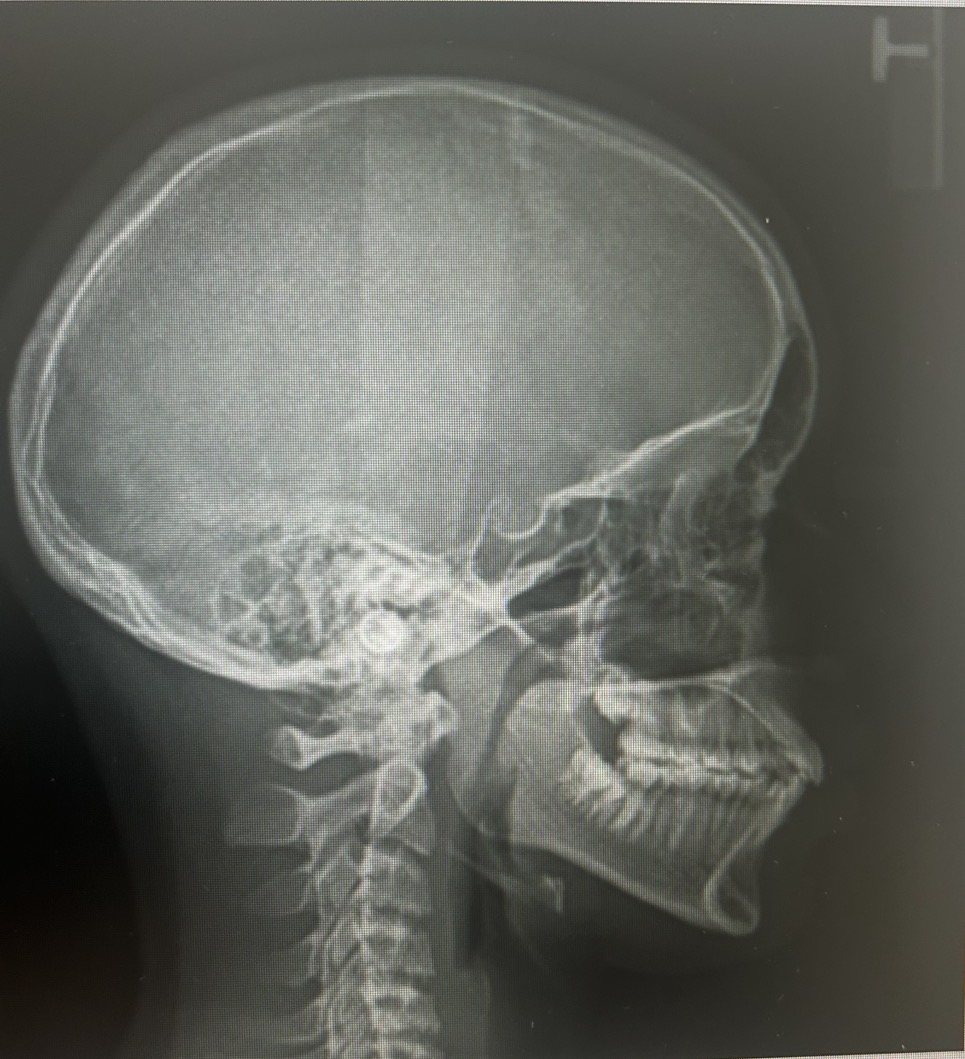

Here are some photos that were taken at the orthodntics. lmk what yall think

In that xray your bite is in the right position you don’t have a deep bite